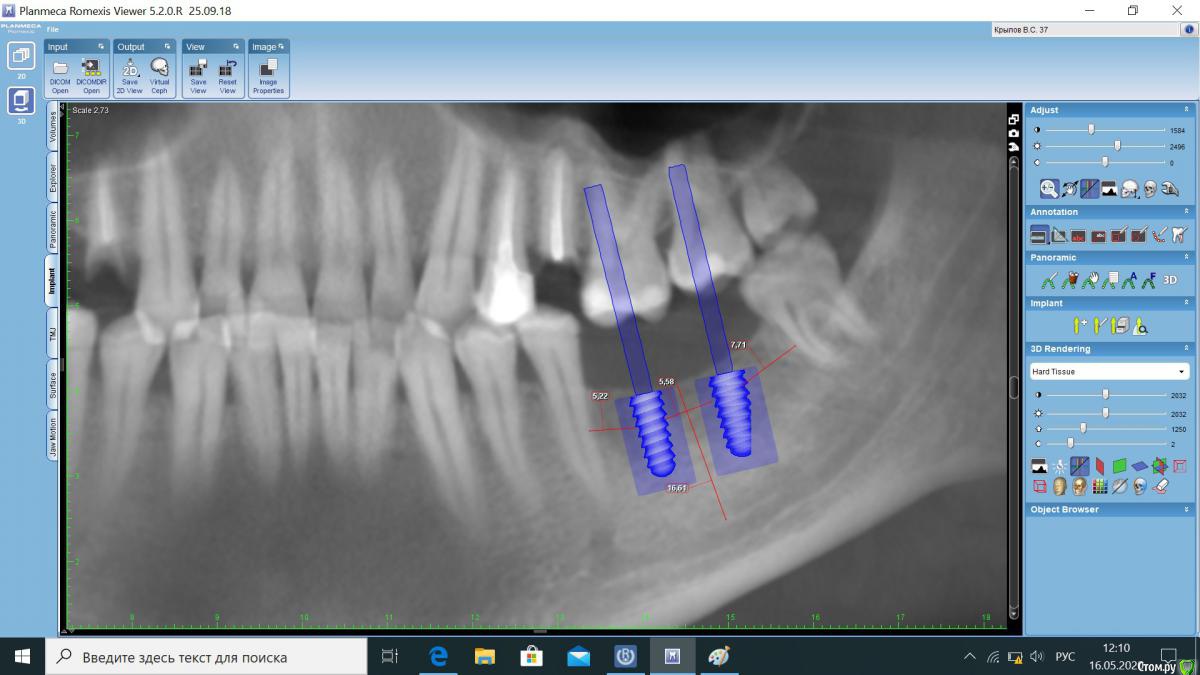

Orhan_dentist125 Опубликовано 16 мая, 2020 Поделиться Опубликовано 16 мая, 2020 Коллеги, доброго времени суток! заканчиваю ординатуру. на неделе будет мой первый опыт установки импланта Штрауман пациенту. Хочу обратиться к докторам за советом и помощью. 1. Правильно ли подобрал размер имплантов? если нет, то скажите какой лучше? импланты будут штрауман2. Расскажите пожалуйста поэтапно какой разрез? и протокол установки, если не сложно. и как и чем шить? я видел много как после установки импланта, подсыпают графт, сверху все это накрывают мембраной и ушивают. делать ли так же? и вообще для чего это делается?3. Одномоменто планирую удалить 14,25 и установить импланты 36,37. первый вопрос касается имплантов 36 и 374. с 4 сегментом планирую работать попозжеприлагаю снимки КТ5. Может стоит заказать хирургический шаблон?Спасибо заранее всем за ответ Ссылка на комментарий

Aquarius Опубликовано 16 мая, 2020 Поделиться Опубликовано 16 мая, 2020 4 на 10 здесь с закрытыми глазами встанут Ссылка на комментарий

krokomot Опубликовано 16 мая, 2020 Поделиться Опубликовано 16 мая, 2020 (изменено) Для установки имплантатов нужно знать размер будущих коронок, судя по снимку 2 полноценных жевательных зуба не влезут или будут маленькими, если планируется в дальнейшем удаление восьмерке, то дистальный имплантат нужно ставить почти в плотную к краю коронки, это нужно учитывать. я бы в данной ситуации сделал разрез, отслоил на полсантиметра в каждую сторону, сделал ложе под имплантат на 1 мм глубже длины имплантата, установил имплантат и формирователь, ушить п-образными, но от плотности кости, формы и типа резьбы имплантата возможно придется модифицировать протокол. Ощущение плотности кости приходит только с опытом. Изменено 16 мая, 2020 пользователем krokomot 2 Ссылка на комментарий